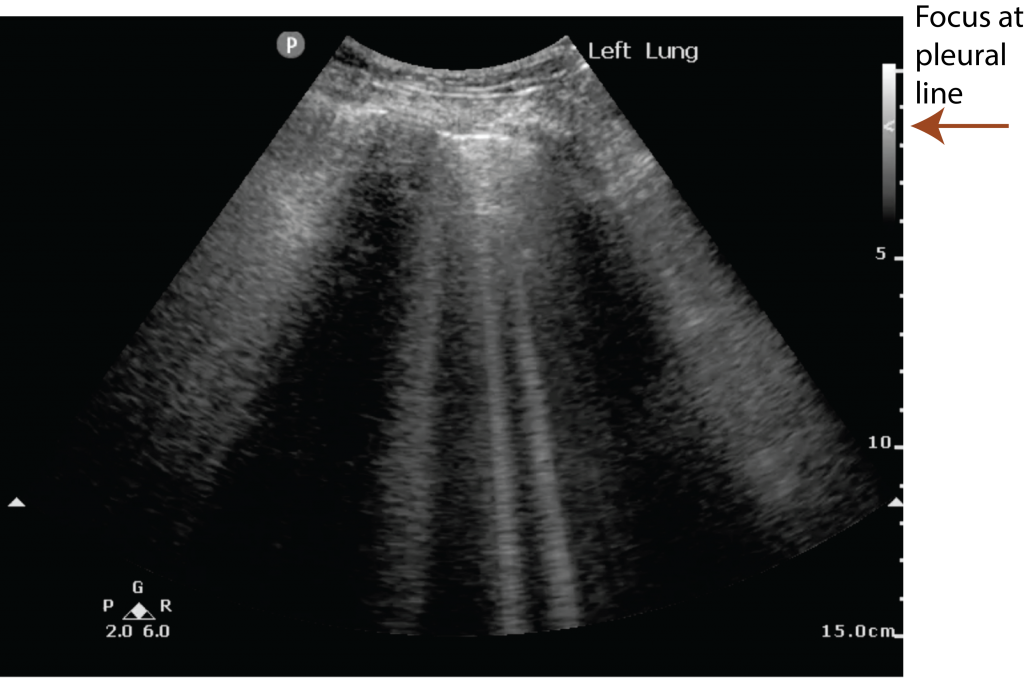

from pocus.sg

ALines Point of Care Ultrasound

ALines Point of Care Ultrasound S Lines Ultrasound Information concerning lines, signs, and lung profiles in this review is based mainly on d. It is imperative to be familiar with ultrasound physics, normal lung. Lichtenstein’s research and book “whole body ultrasound in. On lus, the parietal pleura (outer pleural layer attached to the chest wall) and visceral pleura (inner pleural layer covering the lungs). The ultrasound appearance of. S Lines Ultrasound.